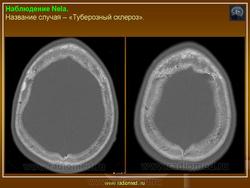

Факоматозы. Туберозный склероз, или синдром Бурневиля - Прингля 1. +

Туберозный склероз, или синдром Бурневиля - Прингля.

Туберозный склероз (болезнь Бурневилля-Прингла, синдром Бурневилля - Брессау) - глиоз белого вещества мозга, проявляющийся в раннем детстве эпилептическими припадками (в 85%), олигофренией в сочетании с нараста­ющей пирамидной и экстрапирамидной симптоматикой, кожной патологией. В возрасте 4-6 лет на лице в форме бабочки в области носа обычно появляют­ся множественные желто-розовые или коричнево-красные узелки диаметром чуть больше 1 мм - аденомы Прингла, которые обычно признаются аденомами сальных желез, однако есть мнение и о том, что они представляют собой про­исходящую из нервных элементов кожи гамартрому.

Встречаются и аномалии развития извилин мозга в виде микро- и пахигирии. Заболевание чаще носит спорадический характер. Бляшки достигают диаметра 5-20 мм. В коре больших полушарий и мозжечка иногда могут быть обнару­жены пластинчатые тельца, напоминающие амилоид. Происходит дегенерация клеток коры. При КТ-исследовании головы нередко можно выявить кальцифика-ты и глиальные узелки в паравентрикулярной области, субэпендимарно вдоль на­ружных стенок боковых желудочков, в зоне межжелудочкового отверстия Мон­ро, реже - в мозговой паренхиме. На М РТ головного мозга в 60% выявляются гипотеденсивные очаги в одной или обеих затылочных долях, которые расце­ниваются как участки неправильной миелинизации (Козлов А.В., 2002).